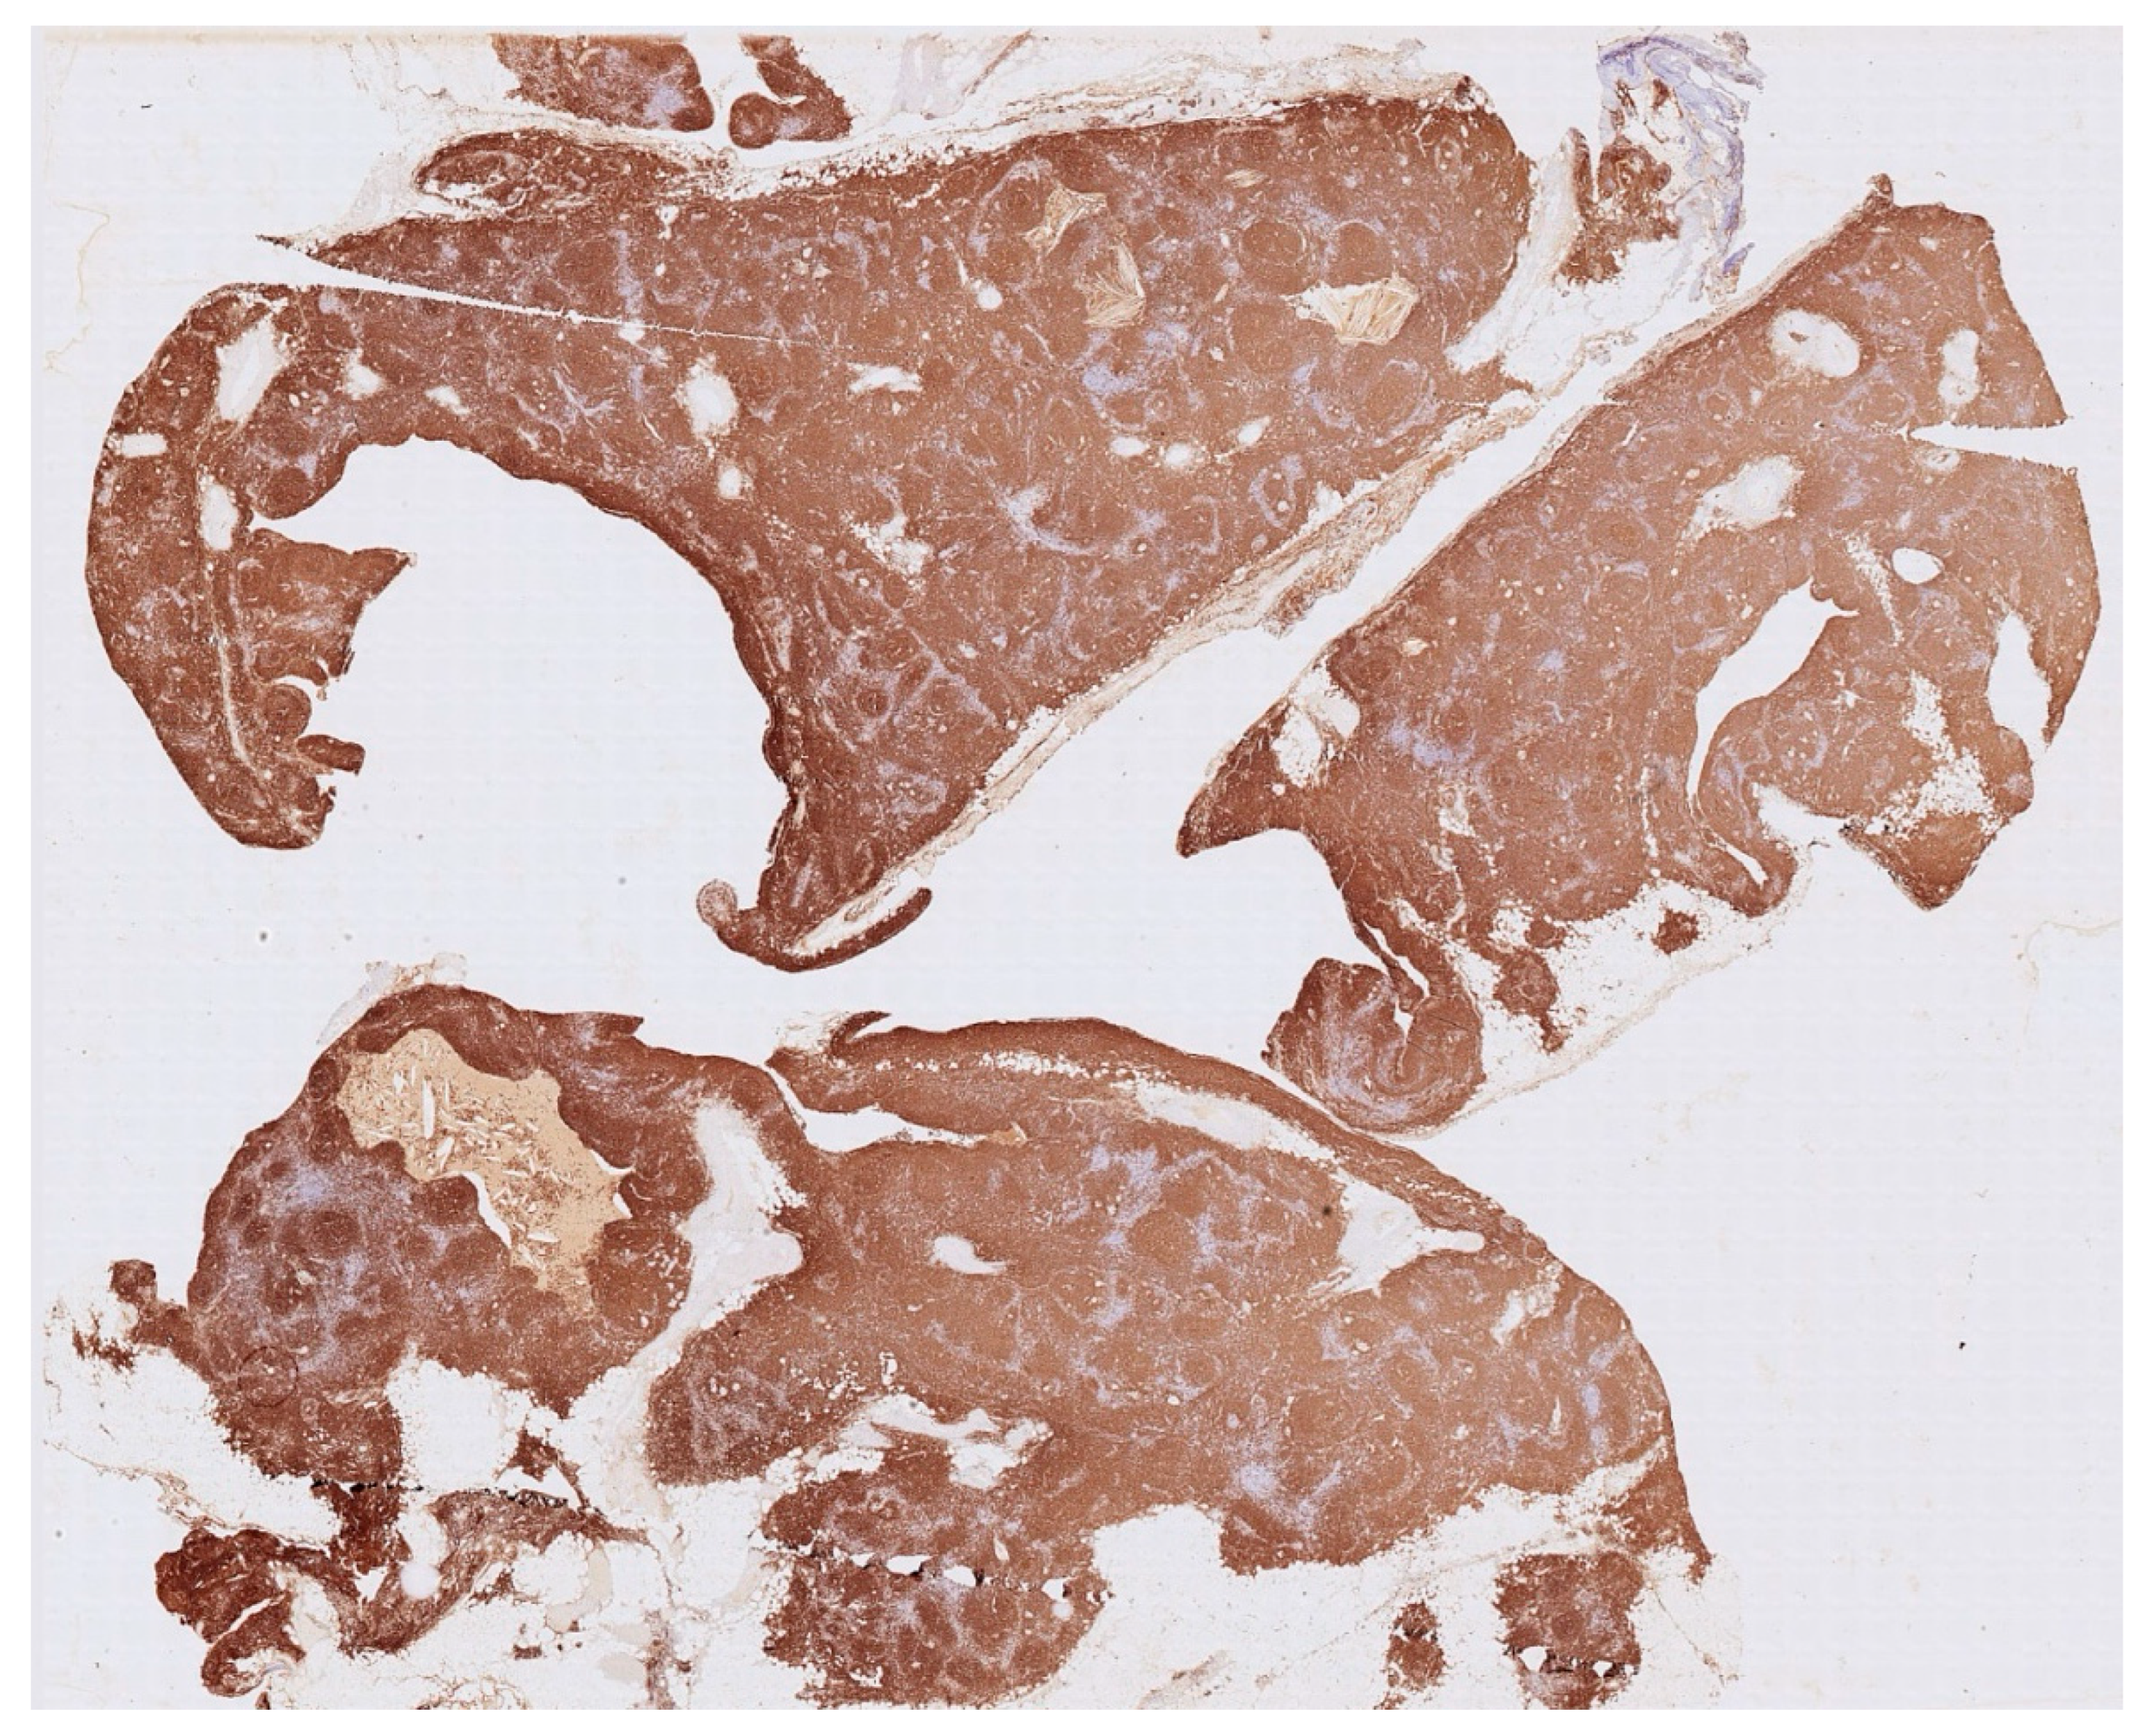

Histology showed an MTC lined by cubic epithelium and rich in lymphoid tissue, organized in germinal centers (CD10+, BCL6+, BCL2−, CD21+, CD23+), and a mantel zone (CD79A+, BCL2+), the interfollicular region represented by T-cell (CD3+), and occasional Hassall’s Corpuscles (

Figure 2,

Figure 3 and

Figure 4).